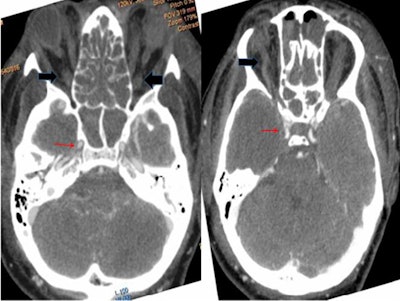

Contrast-enhanced computed tomography (CT) scans and cerebral CT angiography confirmed the diagnosis, revealing poor enhancement of both cavernous sinuses denoting acute thrombosis. A nasal endoscopic exam showed nothing abnormal, and a histopathological exam showed no signs of invasive fungal infection, according to the authors.